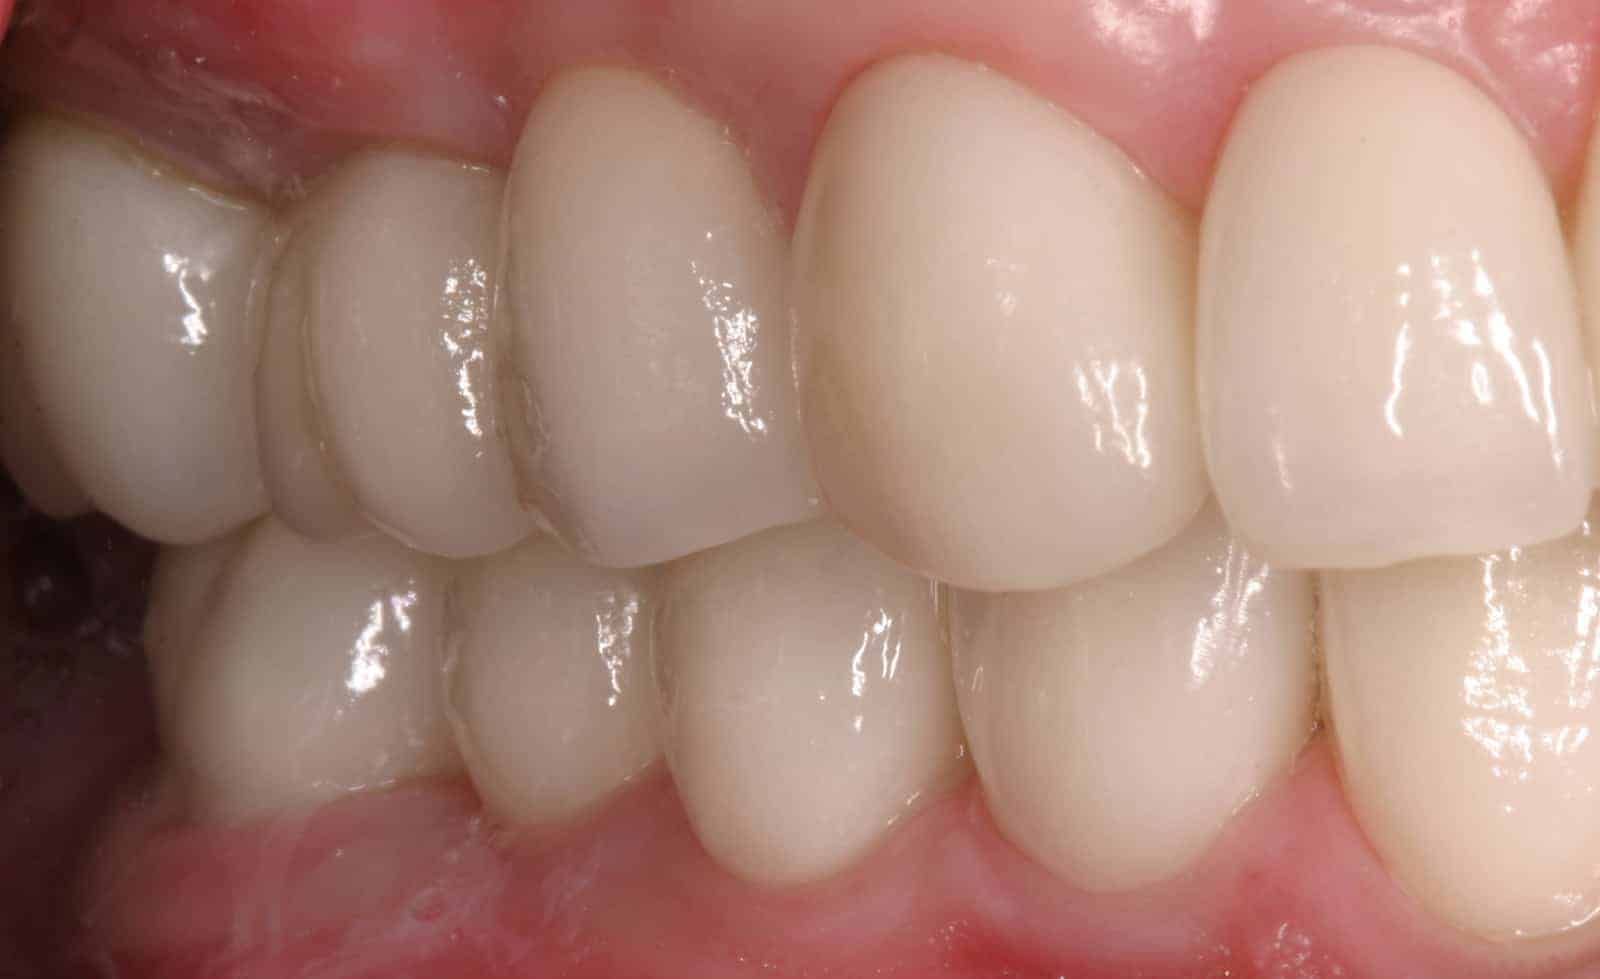

After:Â Implants were then placed by the team oral surgeon utilizing surgical guides fabricated by Dr. Leopardi. Dr. Leopardi then performed a complete dental (full mouth) rehabilitation: full coverage, conservative bonded porcelain restorations on natural teeth; all ceramic implant restorations on the upper lateral incisor implants (sited 7 and 10), porcelain fused to gold implant restorations on implants 3, 14, 19, 21, 23, 25, 28 and 29, at increased occlusal vertical dimension. Patient was restored to full function and aesthetics, significantly improving quality of life.